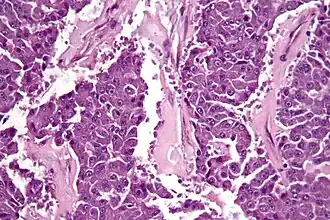

| Micrografia de um carcinoma de células acinares do pâncreas, coloração H&E. | |

Carcinoma de células acinares do pâncreas é um tumor pancreático exócrino raro e maligno. Corresponde a 5% de todos os tumores do pâncreas, sendo o segundo tipo mais comum de cancro do pâncreas.[1]